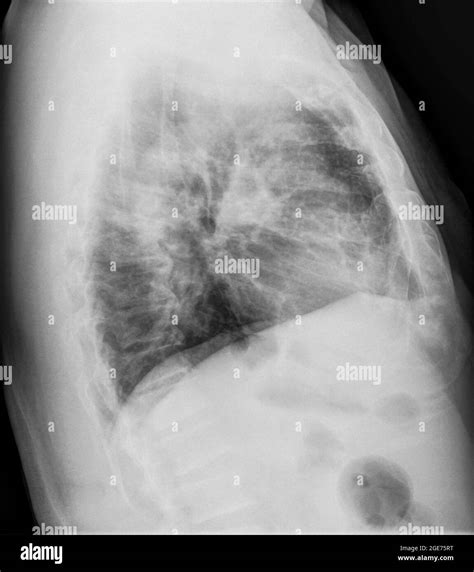

The Normal Lateral Cxr is a diagnostic imaging technique that uses X-rays to create detailed images of the chest, including the lungs, heart, and surrounding structures. This type of X-ray is particularly useful for detecting abnormalities in the chest cavity, such as infections, tumors, and structural issues. The lateral view, which is taken from the side, provides a different perspective compared to the frontal view, allowing for a more thorough examination.

There are several types of chest X-rays, each serving different diagnostic purposes. The Normal Lateral Cxr is often used in conjunction with the frontal view to provide a comprehensive assessment. Other types include:

• Lateral view: Taken from the side, this view complements the frontal views by providing additional details.